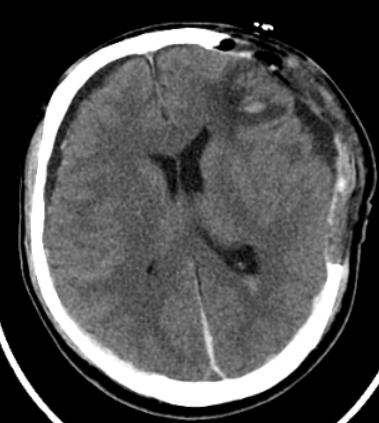

医护人员全程护送,紧急CT检查显示:大脑实质密度减低,左侧额颞顶硬膜下出血、右侧硬膜外血肿、蛛网膜下腔出血,合并右侧颅骨及颞骨多发骨折。最关键的是,CT显示中线结构向右偏移高达12mm(医学上≥5mm即为急需手术的强烈指征,尤其在患者出现意识障碍时)!创伤中心立即启动响应,开通绿色通道。

患者术前CT显示中线偏移,左右侧出血